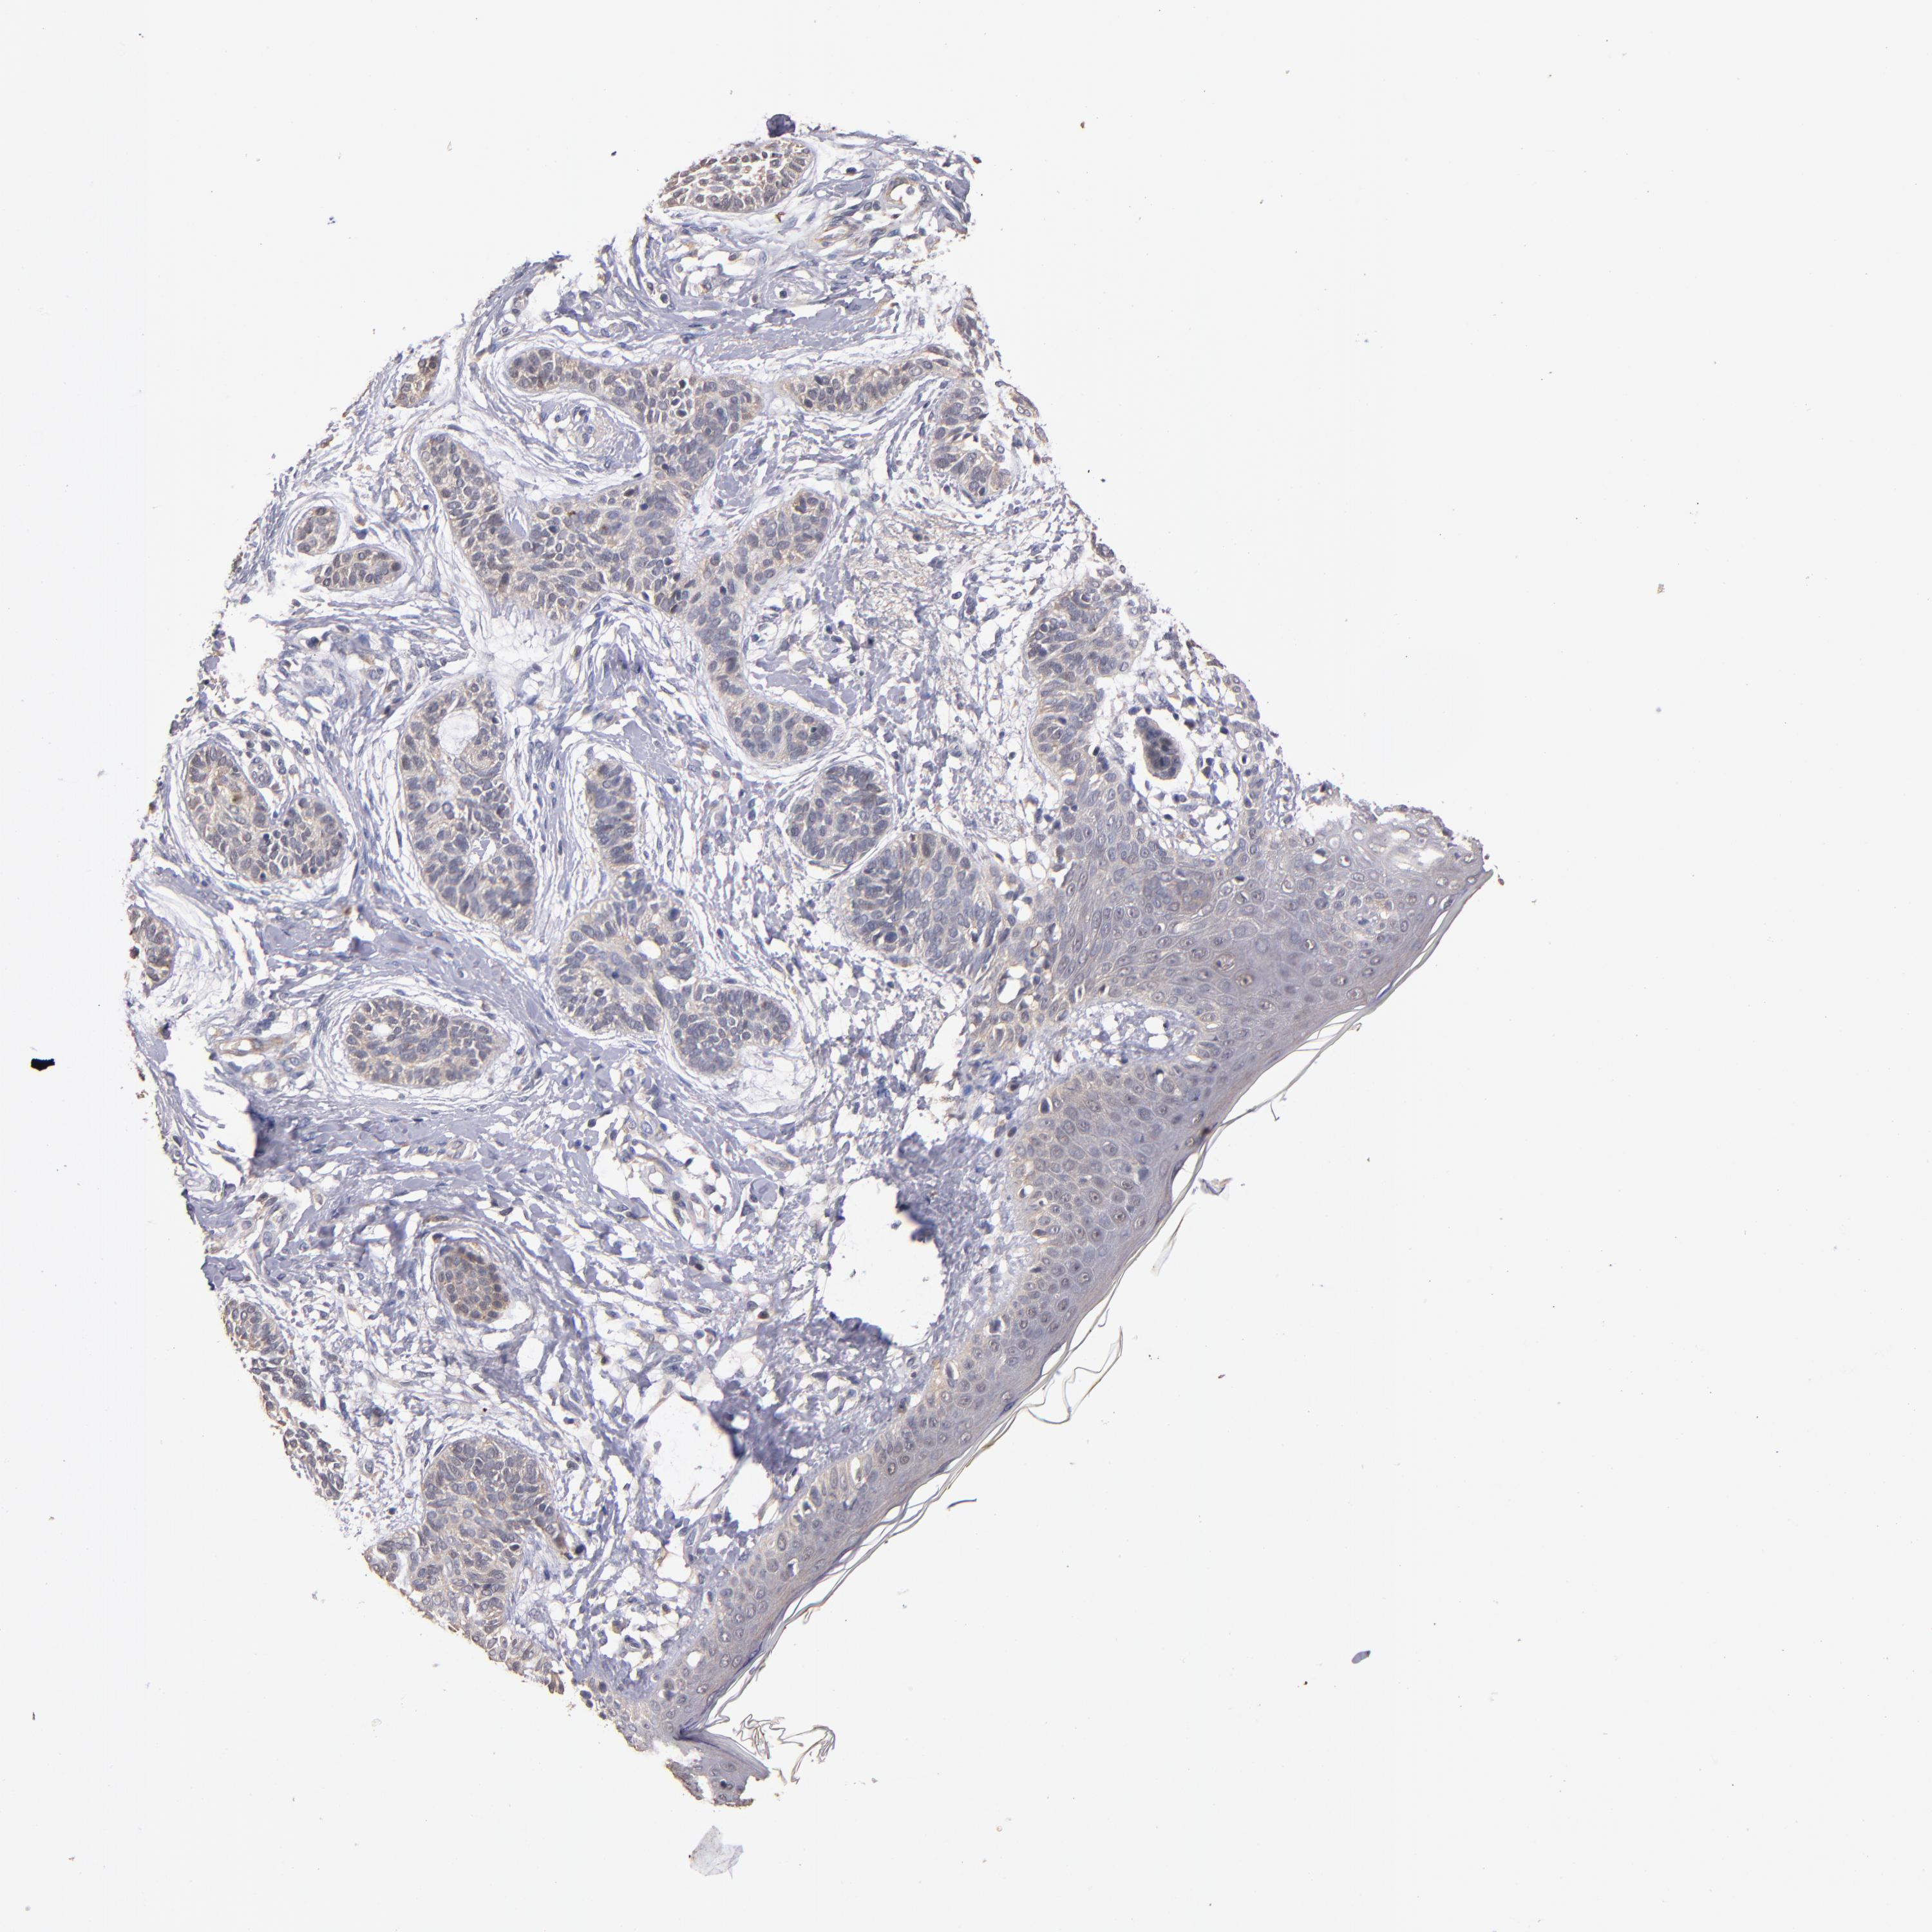

CANCER SKIN CANCER Show tissue menu

Basal cell and squamous cell cancer

SKIN CANCER - Protein expressioni

A mouse-over function shows sample information and annotation data. Click on an image to view it in a full screen mode. Samples can be filtered based on level of antibody staining by selecting one or several of the following categories: high, medium, low and not detected. The assay and annotation is described here.

Each image is clickable and will lead to virtual microscopy that enables deeper exploration of all samples and also displays staining intensity scores, fraction scores and subcellular localization as well as patient and tissue information for each sample.

Antibody HPA003054

Antibody CAB046029

Staining

High

Medium

Low

Not detected

Intensity

Strong

Moderate

Weak

Negative

Quantity

>75%

75%-25%

<25%

None

Location

Nuclear

Cytoplasmic/membranous

Cytoplasmic/membranous,nuclear

Squamous cell carcinoma, NOS

Basal cell carcinoma

Squamous cell carcinoma, metastatic, NOS